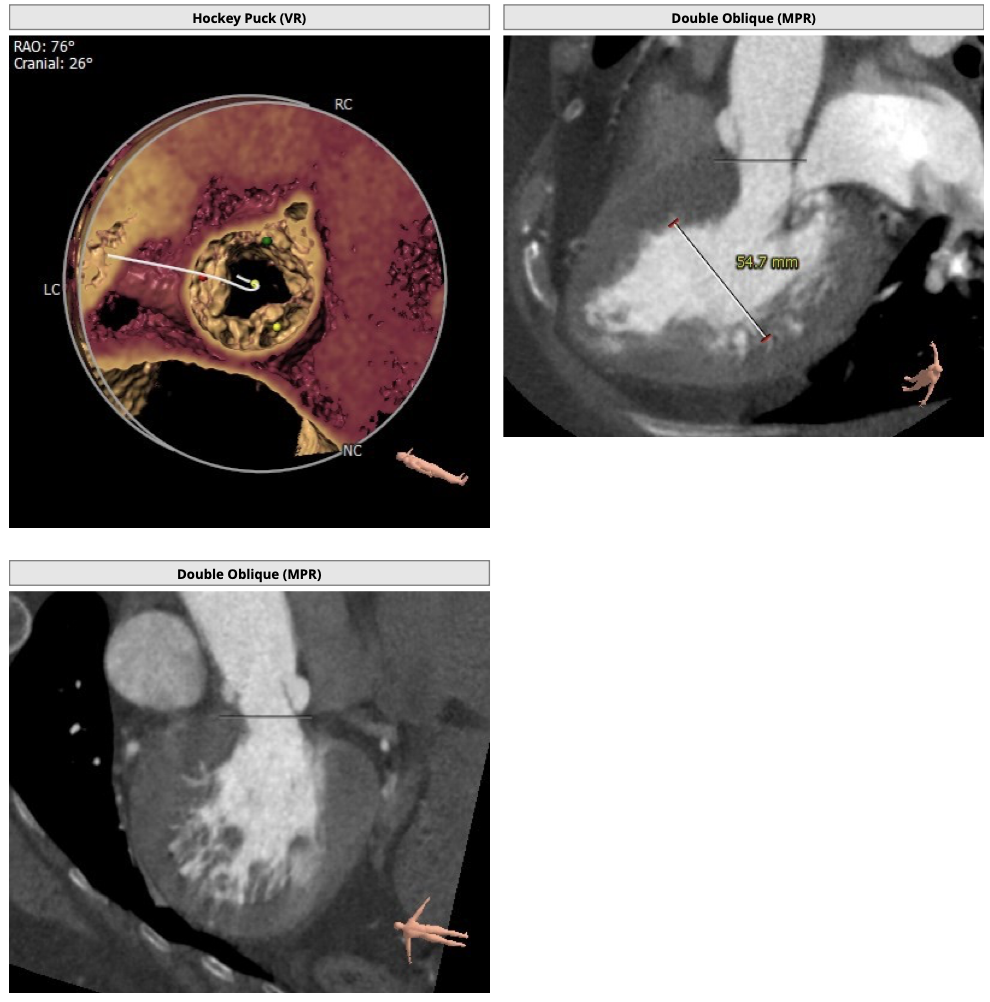

根部造影

定位胶囊腔

释放瓣膜

瓣膜释放至2/3时造影

继续释放瓣膜

瓣膜释放完毕